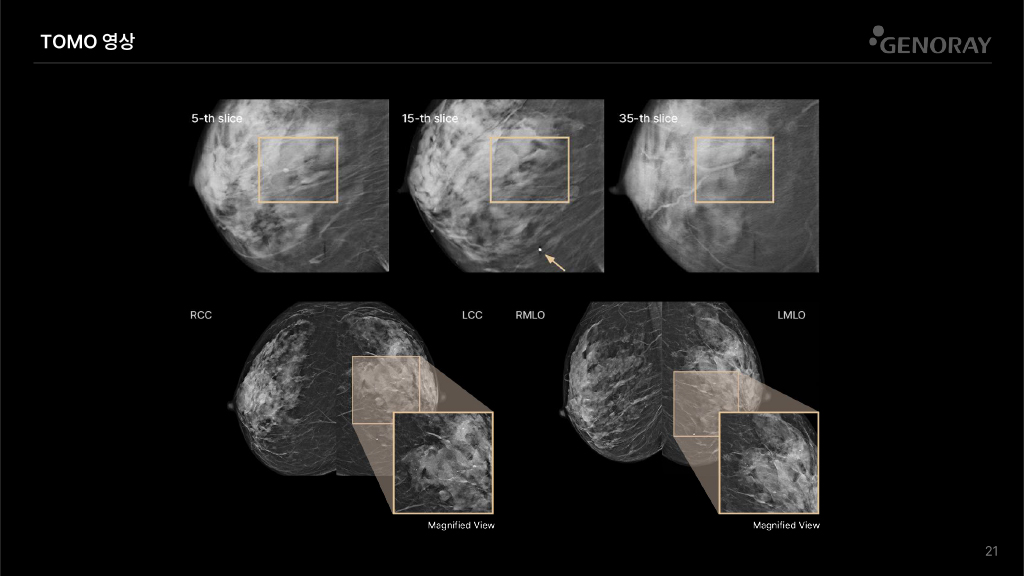

DBT (Digital Breast Tomosynthesis)

Tomosynthesis

- 엑스선 튜브가 유방 위에서 움직이며, 다양한 각도에서 대조도 높은 고화질, 고해상도 영상을 촬영합니다.

- 촬영한 사진들을 3차원으로 재구성하여, 병변의 위치와 상태에 대해 정확한 정보를 제공합니다.